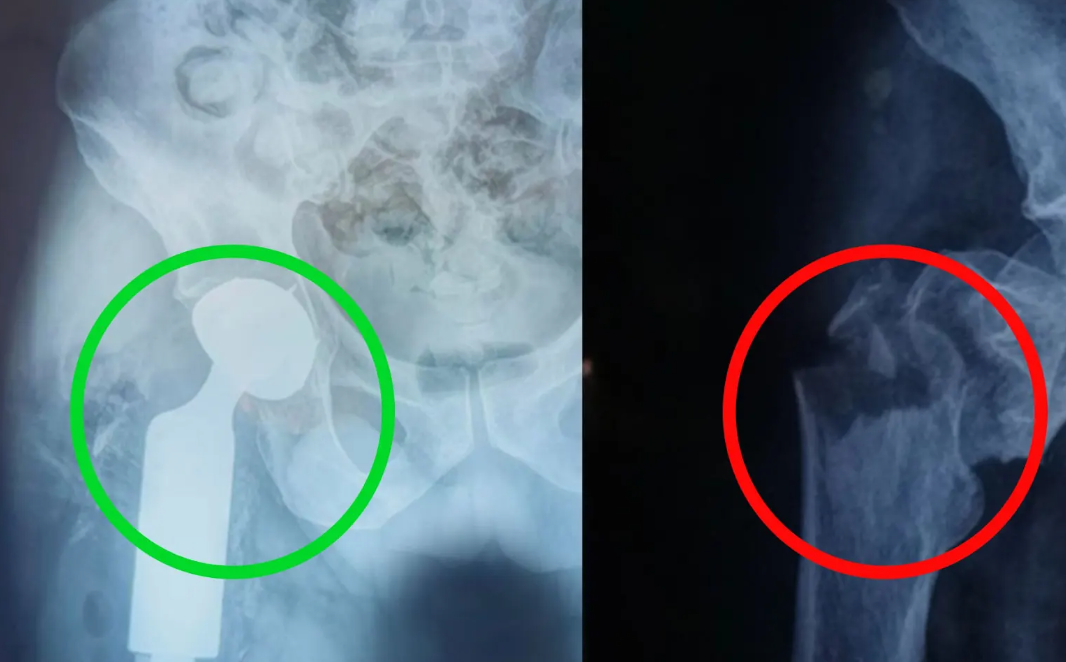

Ciudad de Guatemala, 3 oct (AGN).- El Hospital Nacional de Retalhuleu alcanzó un nuevo hito médico al practicar, con éxito y por primera vez en sus instalaciones, una cirugía de fractura de cadera con colocación de prótesis modular.

El procedimiento fue practicado a un paciente de 74 años con diagnóstico de hipertensión, quien sufrió una fractura compleja.

El traumatólogo y ortopedista Andrés Felipe Giraldo Salas explicó que este tipo de procedimientos, por su alta complejidad, suelen hacerse en hospitales de referencia nacional. Sin embargo, destacó que en esta ocasión fue posible llevarlo a cabo en Retalhuleu.

Lo que queremos evidenciar aquí es que aún con estas fracturas complejas, el hospital cuenta con los medios, el espacio y los recursos para abordarlas con éxito.